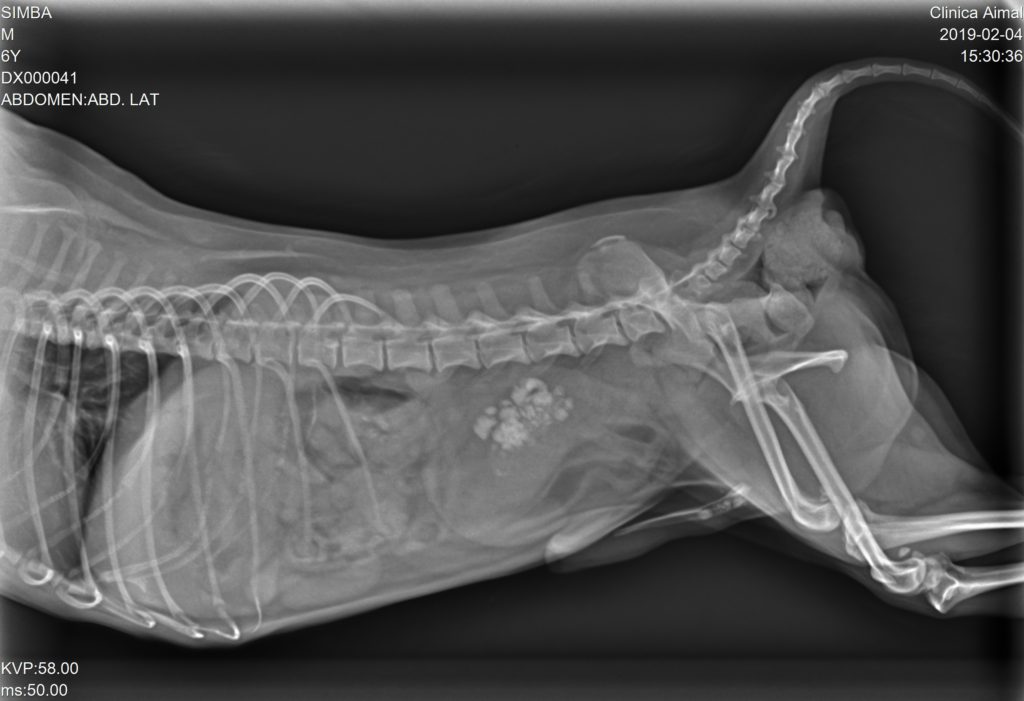

Tres días más tarde realizamos otra Radiografía de control y nos percatamos que algunos urolitos vuelven a estar depositados a lo largo de la uretra, por lo que antes de la cistotomía debemos realizar un sondaje para arrastrar los urolitos de nuevo a vejiga para poder retirarlos mediante la cistotomía.